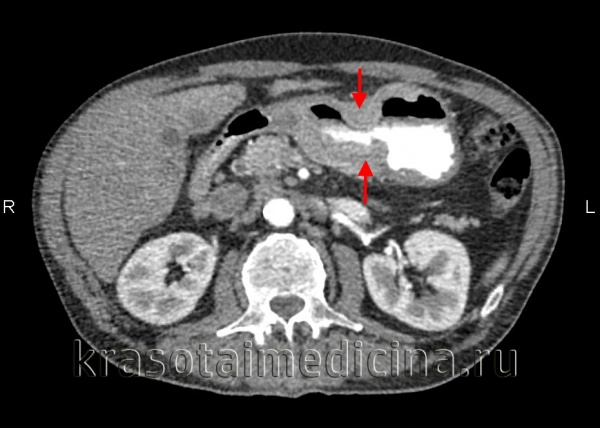

Диагноз устанавливается с учетом анамнеза, клинических проявлений, данных УЗИ органов брюшной полости, МСКТ брюшной полости с контрастированием, цитология асцитической жидкости, полученной при проведении лапароцентеза, и гистологического исследования образца ткани опухоли брюшины, взятого в ходе лапароскопии. В качестве дополнительной диагностической методики может применяться тест на онкомаркеры, позволяющий более точно определять прогноз, своевременно выявлять рецидивы и оценивать эффективность терапии.

- Компьютерная и магнитно-резонансная томография помогают оценить состояние брюшины и внутренних органов, выявить патологические образования, оценить степень распространения рака.

Обычно врачи-онкологи устанавливают диагноз на основании таких признаков, как асцит, утолщение брюшины, появление на ней узелков, смещение, сдавление петель кишки, патологические изменения со стороны печени и складок брюшины — сальников.